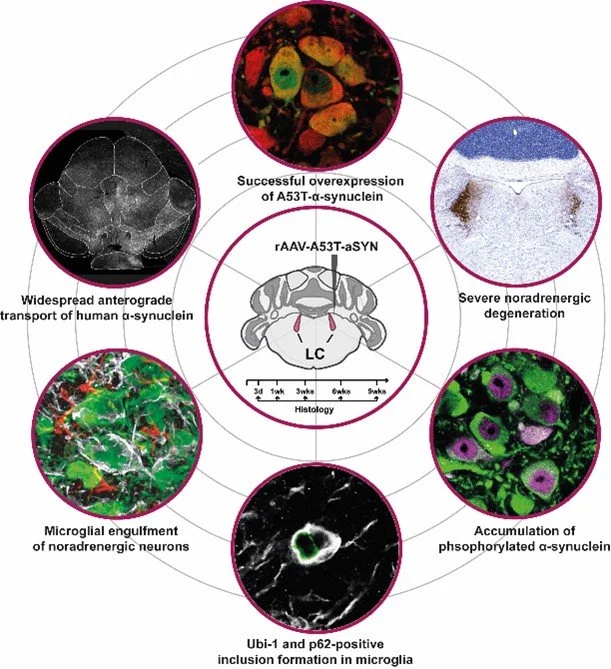

DEVELOPMENT OF NEW PARKINSON’S DISEASE MODELS

Robust disease models are at the core of high-quality translational Parkinson’s disease research. Scientists at the CNP lab are continuously making progress in further characterizing the two central α-synuclein based Parkinson’s disease models: The α-synuclein preformed fibril model and the viral vector based α-synuclein overexpression model.